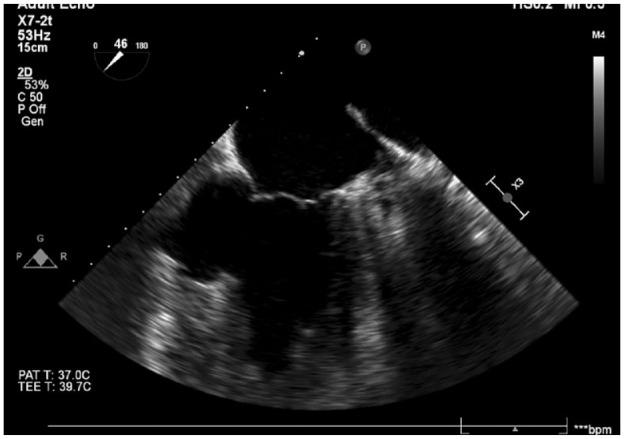

Ventricular septal defect (VSD) represents a severe complication that may manifest after a myocardial infarction (MI), typically occurring between 2 and 7 days later. Due to advancements in reperfusion management, the incidence of VSDs after MI has become very rare, occurring in approximately 0.2% of MIs. The current guidelines recommend urgent post-infarction VSD (PI-VSD) closure. We report a case of a patient with a VSD, which was diagnosed 2.5 years after MI. At the time of acute inferior MI, the patient was managed with primary percutaneous intervention in the culprit artery, and 1 month later coronary artery by-pass grafting (CABG) was completed. Twenty and thirty months after AMI patient presented with ventricular tachycardia (VT). Following the second VT episode patient was hospitalized for further examination. Echocardiography revealed the presence of VSD at the site of inferioseptal wall aneurysm. An ICD was implanted owing to recurrent malignant rhythm disorders. In conclusion, although the PI-VSD might have been overlooked and the patient missed the chance of concomitant CABG and VSD repair, this case has reached a 3-year survival, which appears to be the longest survival recorded in a medically treated patient with PI-VSD.